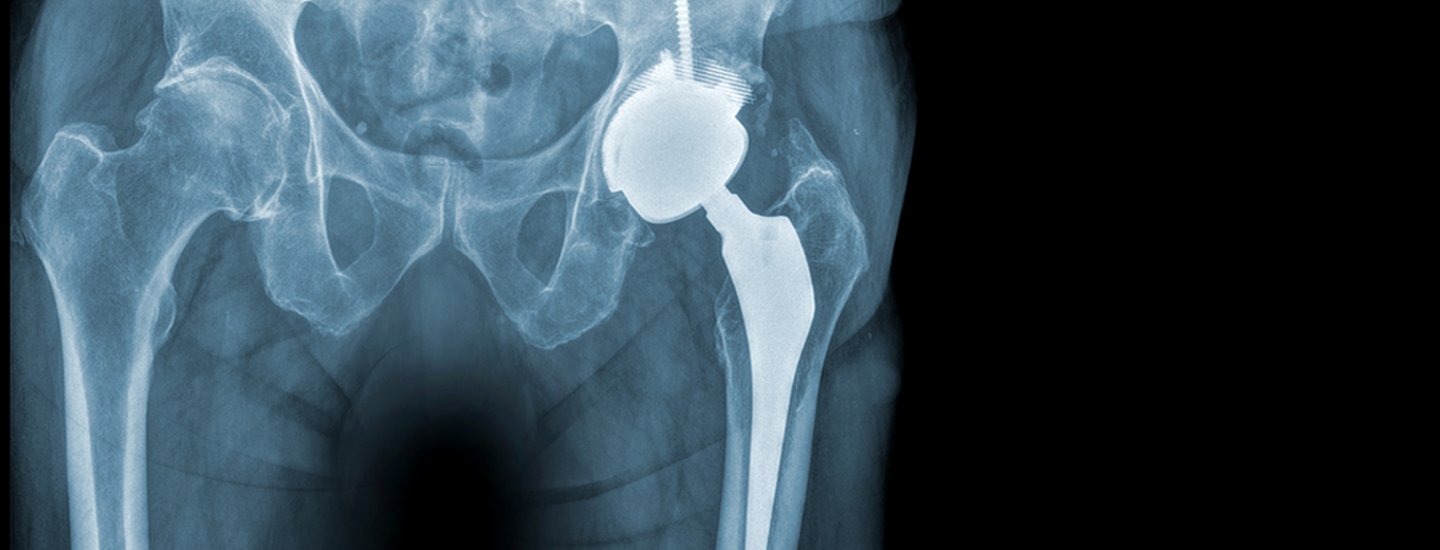

Muskelschonende Chirurgie, knochenschonende Implantate

Die Implantation eines künstlichen Hüftgelenks gehört heute zu den erfolgreichsten Operationen der modernen Medizin. In der orthopädischen Klinik des Spitals Limmattal wird dafür standardmässig der minimalinvasive vordere Zugang zur Hüfte verwendet, der sogenannte «Direct Anterior Approach».

Er gilt als besonders muskelschonend, da die Operation zwischen den wichtigen Muskeln erfolgt und diese nicht durchtrennt werden müssen. Das umliegende Gewebe wird geschont und viele Patientinnen und Patienten können nach der Operation bereits wieder unter voller Belastung mobilisiert werden. In der Regel genügt ein Hautschnitt von weniger als zehn Zentimetern.

Auch bei der Wahl der Implantate wird im LIMMI auf moderne, knochensparende Prothesen gesetzt. Ziel ist es, so viel gesunden Knochen wie möglich zu erhalten. Moderne Implantate ermöglichen in vielen Fällen eine stabile und natürliche Gelenkfunktion über viele Jahre bis Jahrzehnte hinweg.